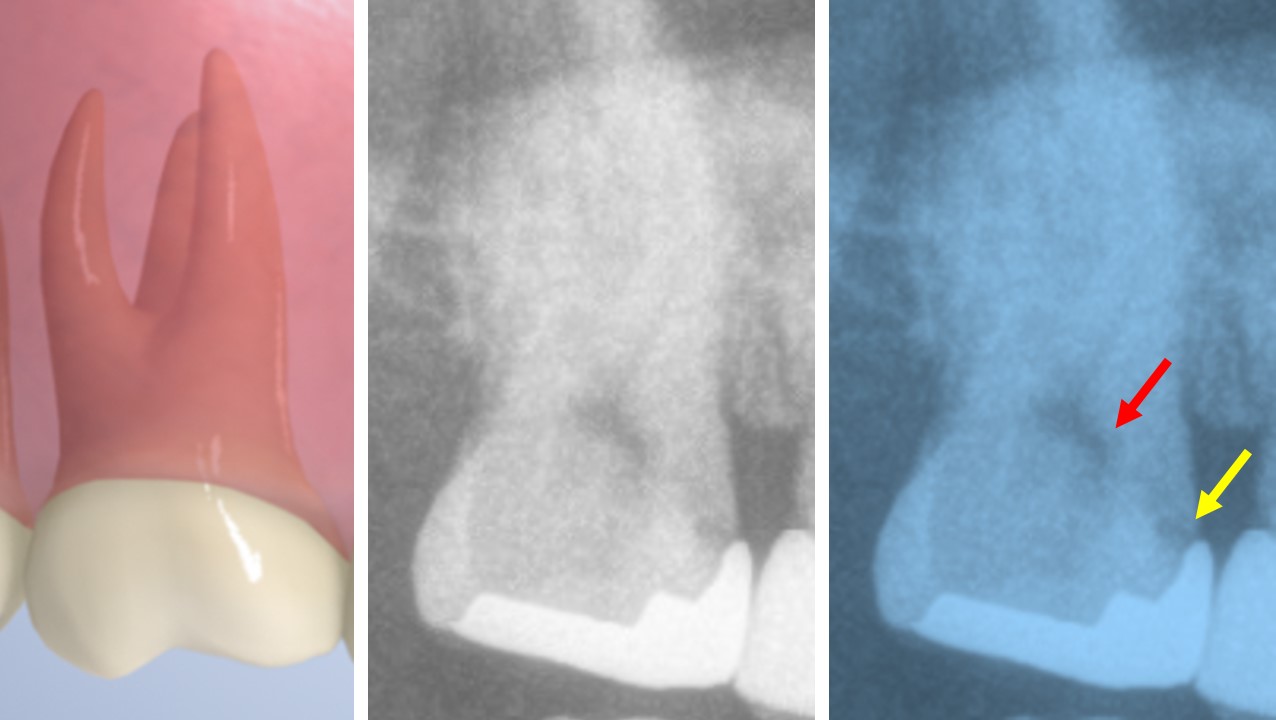

都内初診時レントゲン画像 深いむし歯 MTAで神経を残す 症状なし 都内港区内幸町新橋虎ノ門日比谷霞ヶ関歯科歯医者

都内初診時レントゲン画像 深いむし歯 MTAで神経を残す 症状なし マイクロスコープ画像 都内港区内幸町新橋虎ノ門日比谷霞ヶ関歯科歯医者